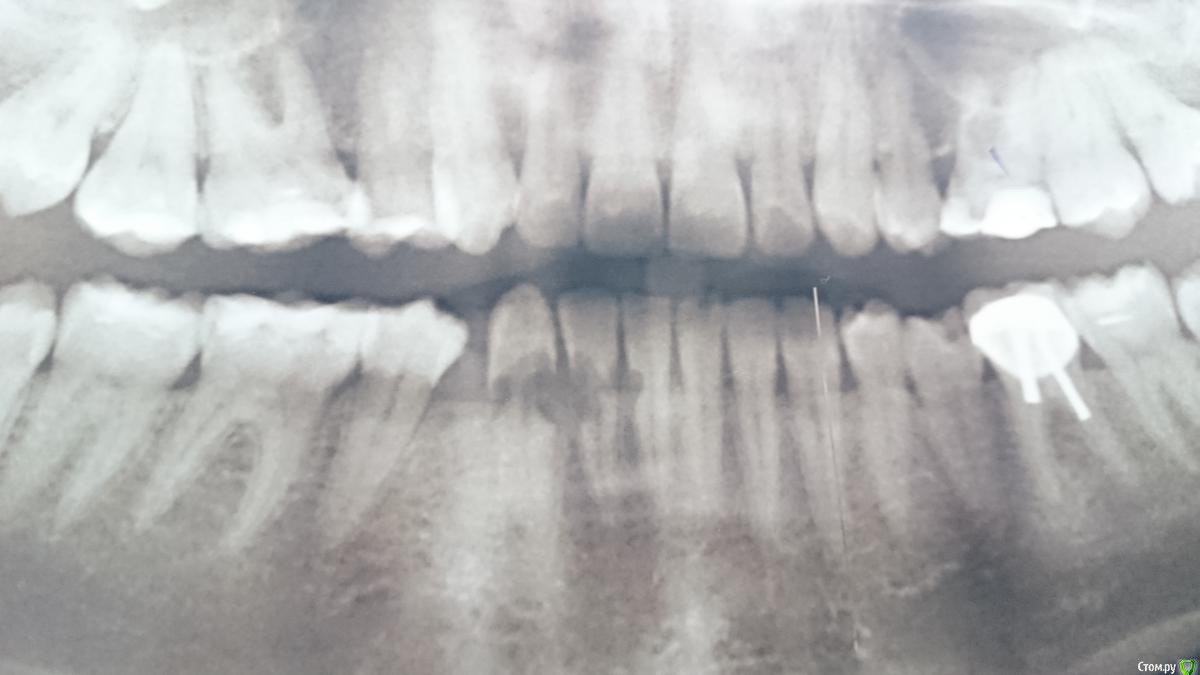

lightella Опубликовано 6 февраля, 2018 Поделиться Опубликовано 6 февраля, 2018 Здравствуйте, коллеги. В клинику обратилась пациентка 1989г.р.Орто 2015г.А это уже 2017Девушка в отчаянии, мы тоже че то приуныли.Кто может - пожалуйста, поделитесь опытом или информацией. Ссылка на комментарий